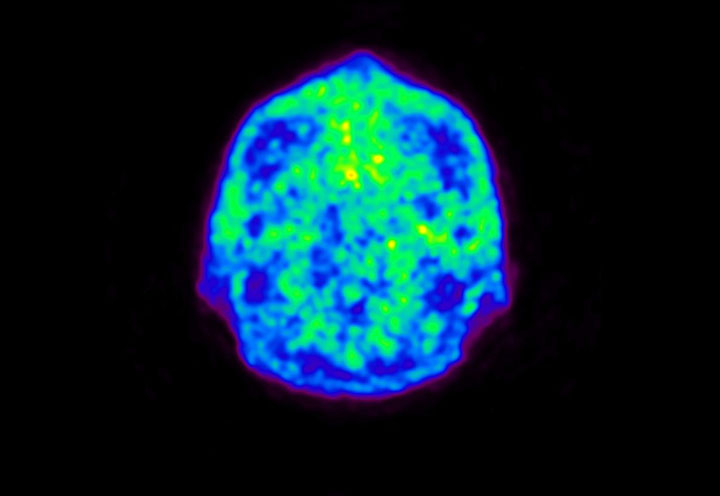

Head / Case5 : Amyloid

Coronal

Courtesy : Kindai University Hospital

- Imaging protocol

- Injected dose: 4.27 MBq/kg, 18F-Flutemetamol

- Uptake time: 99 minutes

- Scan time: 20 minutes